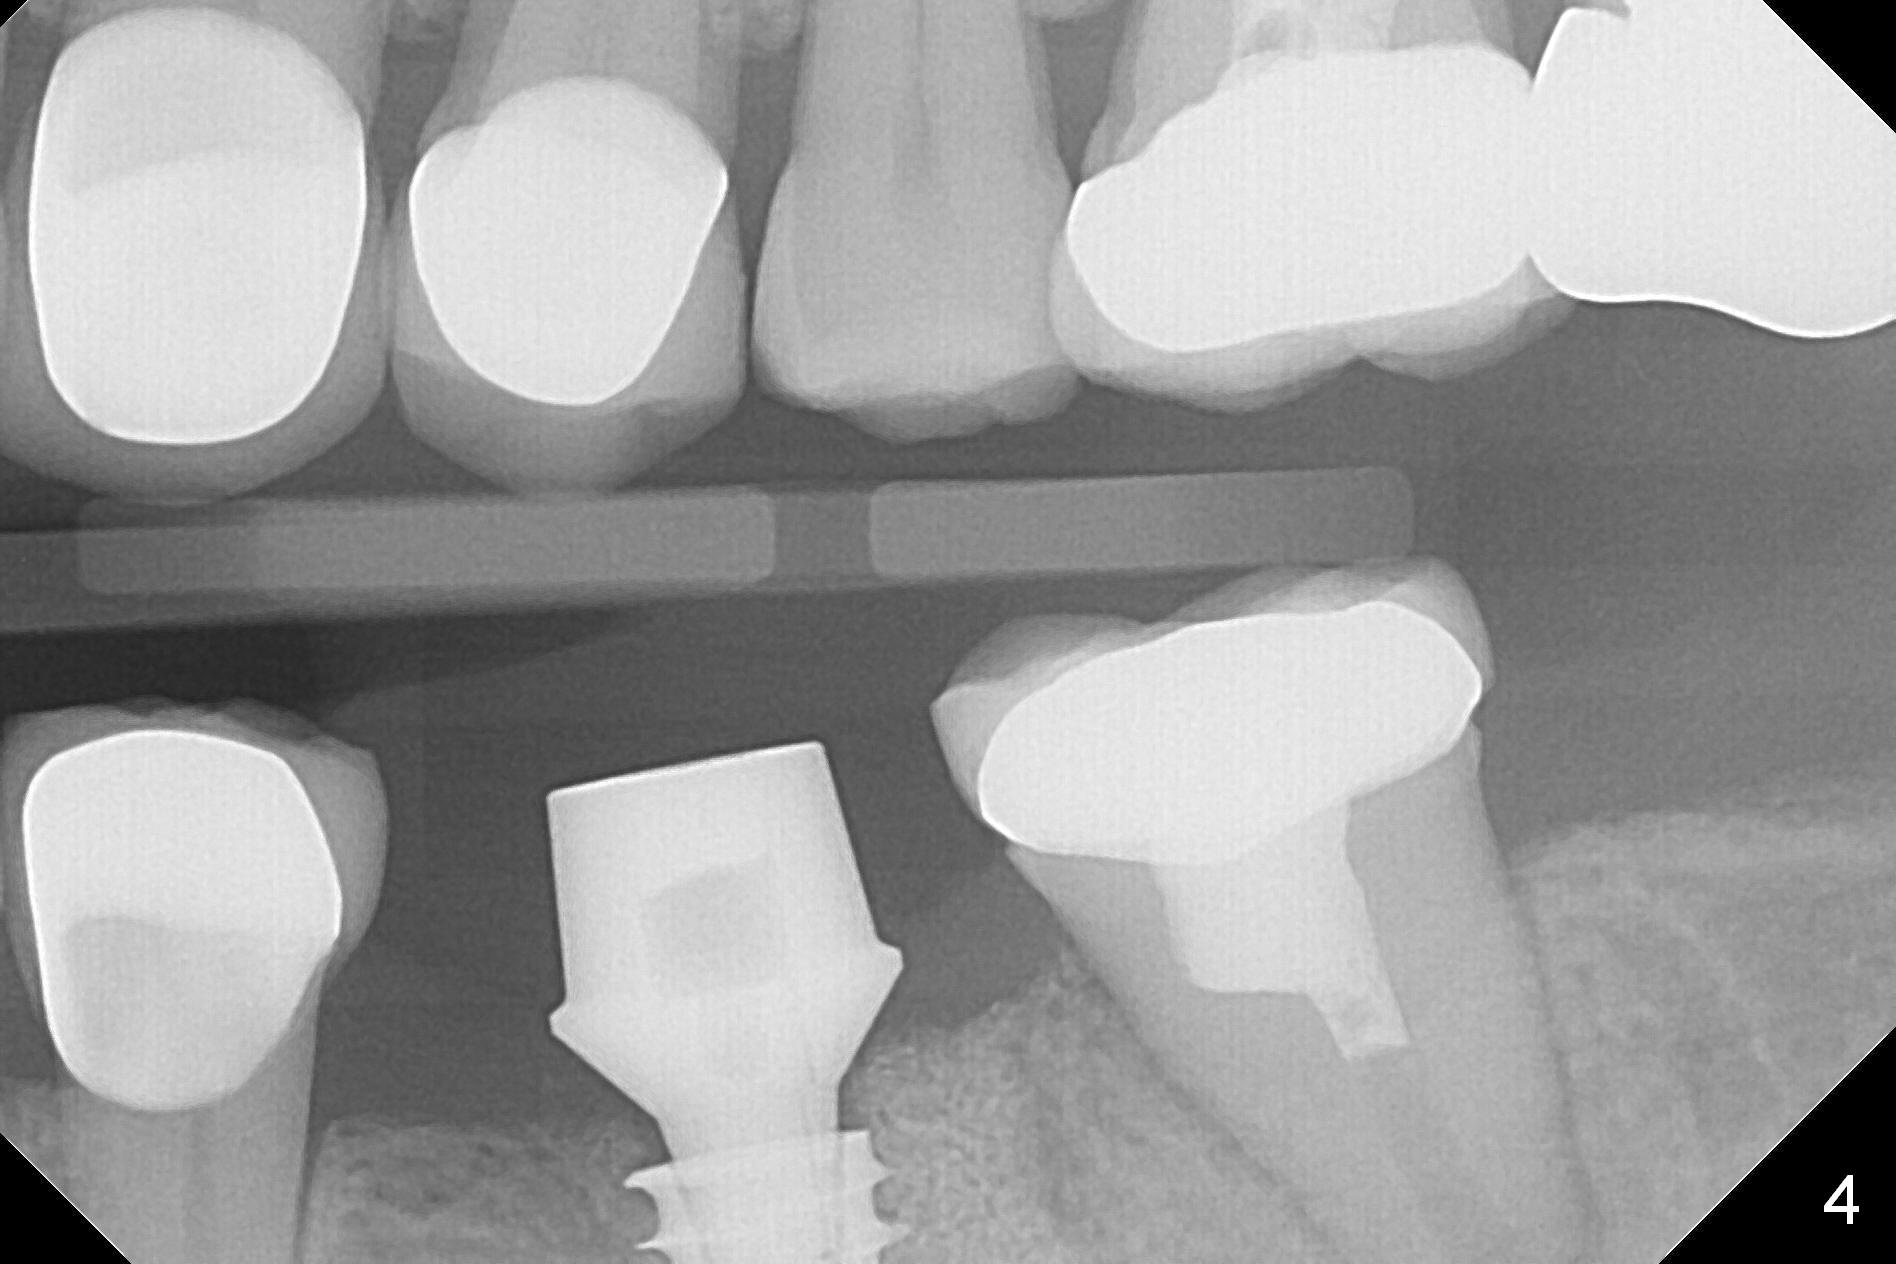

After making a 10 mm incision at the site of #19, #15c blade is used as an osteotome to start bone expansion, followed by Magic Split and Magic Expander (ME, 3 mm in diameter).  The depth is approximately the bottom of the mesial socket.  The osteotomy beyond the socket has to be done with 1.6 mm pilot drill (Fig.1) in combination of ME.  Following ME 4.3 mm and Magic Drill (MD) 3.8 mm for 15 mm (gingival level), a 4.5x11 mm dummy implant is placed with 50 Ncm (Fig.3); the implant looks narrow for the edentulous space.  After ME 4.8, MD 4.3 for 13 mm and Final Drill for 15 mm, a 5x11 mm IBS is inserted with >50 Ncm (Fig.3).  With 2 more turns of the implant, a 6.5x4(2) mm abutment is placed (Fig.4).  Periodontal dressing is applied around the abutment for additional retention.  A provisional is fabricated 3 weeks postop.  The provisional and abutment are loose 4 months postop (Fig.5).  After retightening the abutment, impression is taken for final restoration.  There is no bone loss 1 year 3 months post cementation (Fig.6).  After use of #100 file (Fig.7), the canal is debrided with #140 file with 1.5 mm shorter in working length with placement of Calcium Hydroxide paste.  Pain gets worse post RCT retreatment. There is limited native bone for primary stability when an immediate implant is placed (red dashed line: the superior border of the Inferior Alveolar Canal).  Prepare IS regular and extra wide kits and tissue-level implants (>5 mm).  Socket preservation may be done instead.  If the socket is large and the vein is not so small, prepare PRF.  In fact blood drawing fails.  When the tooth is extracted, it is sensitive to remove granulation tissue.  Socket preservation is done with Vanilla graft at #18 (Fig.8); there is ~3.5 mm bone between the bottom of the single socket and the Inferior Alveolar Canal (red dashed line).  The socket at #18 seems to have healed 4 months post extraction (Fig.19), but the bone height appears to have been reduced (compare Fig.10,11).  The buccolingual width is also decreased (Fig.12,13).  A 4.5 or 5.0x10 mm implant is appropriate for the site (Fig.14).  There is no bone loss at #19 (which may be associated with the bone expansion) 1.5 years post cementation (Fig.15).  Therefore the osteotomy at #18 will be assisted with bone expanders after 2.2 mm drill.